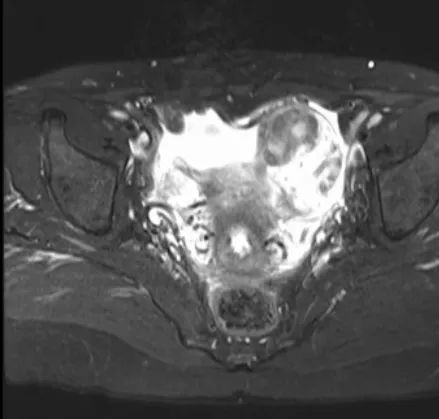

▲ 磁共振图像

近日,妇科接诊了一位46岁的女患者,因下腹剧烈疼痛半天入院,无畏寒、发热,无异常阴道流血,无腹泻。妇检子宫压痛明显。查妊娠试验及C反应蛋白均正常。B超及磁共振提示子宫肌瘤大小约6x5cm。考虑腹痛原因为子宫肌瘤蒂扭转可能性大,予紧急行腹腔镜探查术。术中见肿大坏死的带蒂浆膜下子宫肌瘤6x5cm,予行肌瘤切除,病理学回报子宫平滑肌瘤(大面积梗死,符合扭转的临床诊断)。